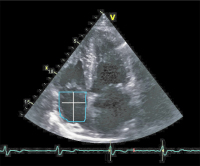

RVOT

Abbildung 4: Vermessung des proximalen RVOT-Durchmessers im parasternalen Kurzachsenschnitt.